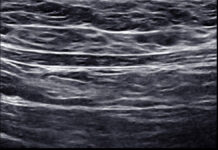

Ultrasonografia. Nowoczesne narzędzie podnoszące bezpieczeństwo w zabiegach estetycznych

Współczesna kosmetologia estetyczna coraz częściej sięga po technologie, które jeszcze niedawno były domeną medycyny. Ultrasonografia, znana głównie z diagnostyki organów wewnętrznych, zyskuje dziś status...